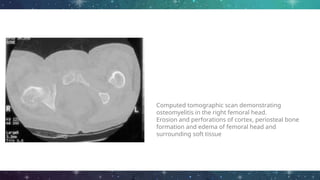

CT scan

● Superior than both MRI and plain radiography in depicting bony

margins

● Identifying sequestrum and involucrum

● Sensitivity and specificity is low (67% and 50% respectively)

● Limitations:

○ Does not exclude early osteomyelitis

○ Artifact when metallic implants are present

Computed tomographic scan demonstrating

osteomyelitis in the right femoral head.

Erosion and perforations of cortex, periosteal bone

formation and edema of femoral head and

surrounding soft tissue